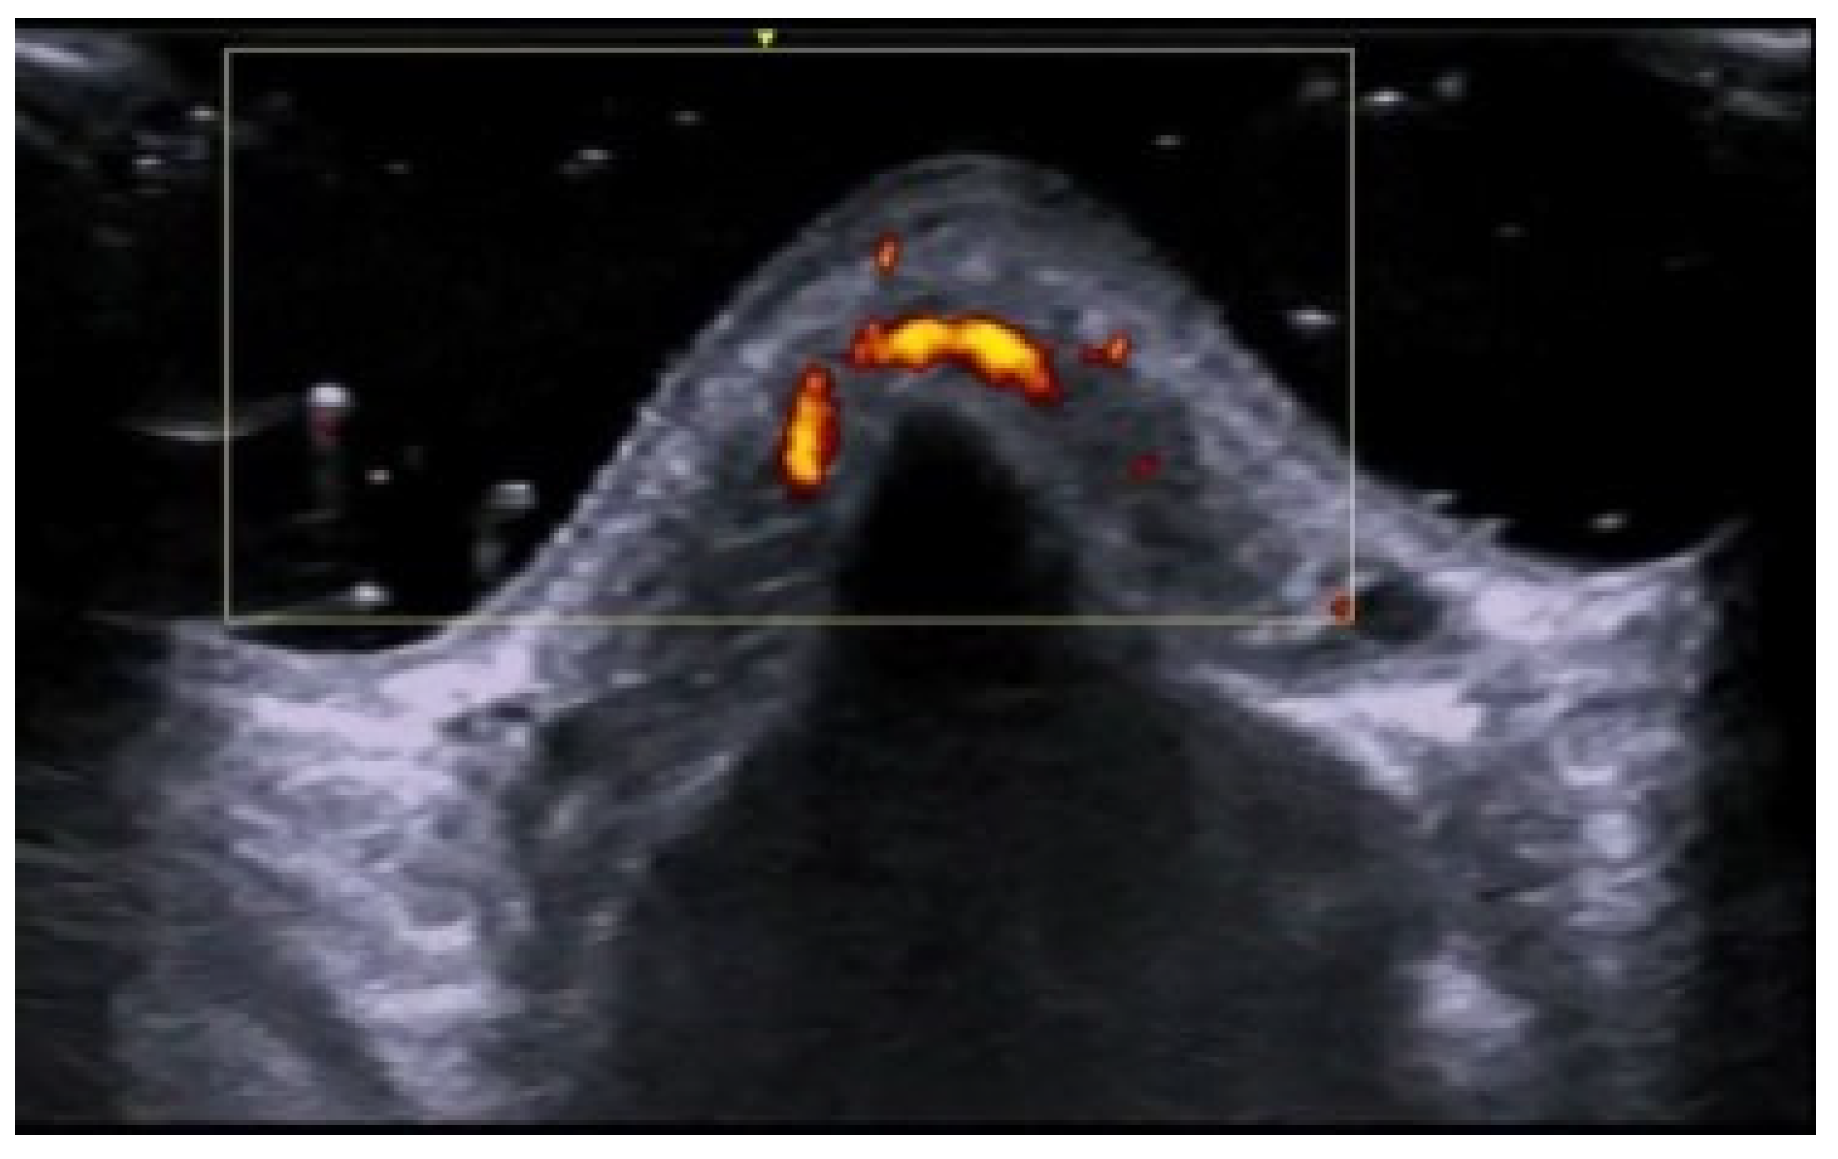

- Parra-Cares, J.; Wortsman, X.; Alfaro-Sepúlveda, D.; Mellado-Francisco, G.; Ramírez-Cornejo, C.; Vera-Kellet, C. Color Doppler Ultrasound Assessment of Subclinical Activity with Scoring of Morphea. J. Cutan. Med. Surg. 2023, 27, 454–460. [Google Scholar] [CrossRef] [PubMed]

- Wortsman, X.; Vera-Kellet, C. Ultrasound Morphea Activity Scoring (US-MAS): Modified US-MAS. J. Ultrasound Med. 2023, 42, 2447–2450. [Google Scholar] [CrossRef] [PubMed]

- Vera-Kellet, C.; Meza-Romero, R.; Moll-Manzur, C.; Ramírez-Cornejo, C.; Wortsman, X. Low effectiveness of methotrexate in the management of localised scleroderma (morphea) based on an ultrasound activity score. Eur. J. Dermatol. 2021, 31, 813–821. [Google Scholar] [CrossRef]